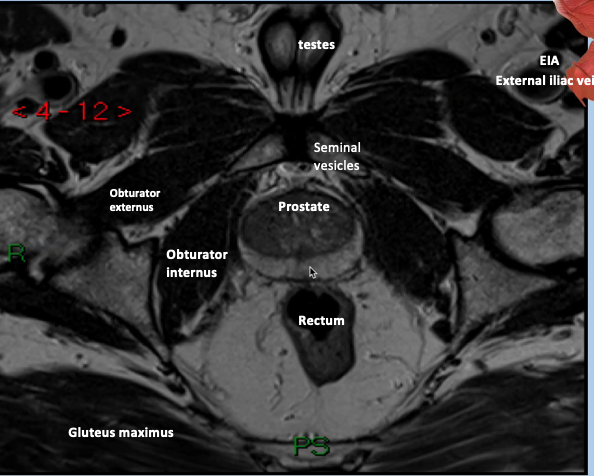

What type of imaging modality is this & fill in the blanks

MRI prostate, axial